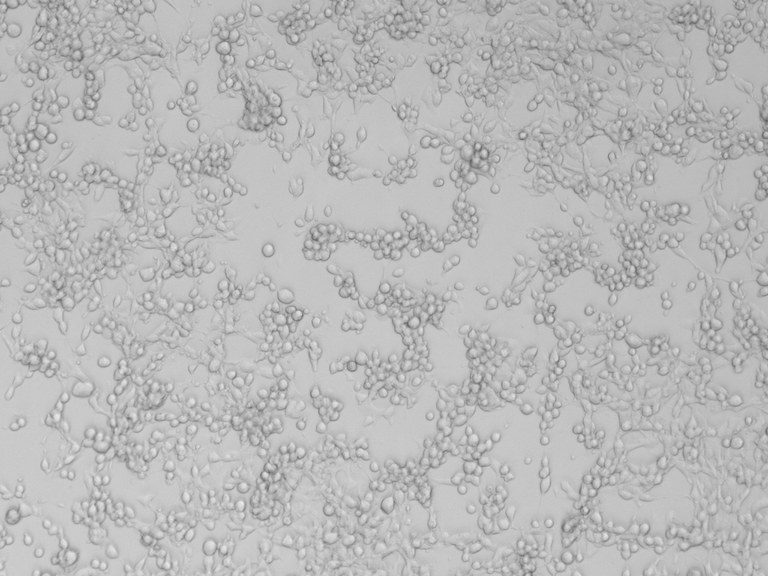

Pesquisadores e MCTI debatem varíola Símia e a ações da CâmaraPox MCTI

Câmara reúne especialistas de universidades brasileiras para pesquisar o comportamento do vírus e sintomas

monkeypox.jpeg

Pesquisadores e o secretário de Pesquisa e Formação Científica do Ministério da Ciência, Tecnologia e Inovação (MCTI) dialogaram em uma live, na segunda-feira (24), sobre os estudos realizados pela Câmara Técnica Temporária de pesquisa denominada CâmaraPox MCTI. A câmara reúne oito especialistas da Universidade Federal de Minas Gerais (UFMG), Universidade Federal do Rio de Janeiro (UFRJ) e Universidade Feevale.

Eles apresentaram os projetos que vêm sido desenvolvidos e falaram das ações que irão ser implantadas nas próximas semanas. O secretário de Pesquisa e Formação Científica do Ministério da Ciência, Tecnologia e Inovação (MCTI) explicou que houve um aumento significativo de casos .

O trabalho do grupo é centrado na definição de prioridades de ações de P,D&I para a superação de lacunas de conhecimento sobre a doença bem como para o desenvolvimento de tecnologias para o enfrentamento da mesma. Até o momento já foram produzidos três informes da Rede, os dois primeiros informando sobre os aspectos gerais do vírus, seus sintomas, diagnóstico e manejo e o terceiro já elencou as principais lacunas de conhecimento que precisam ser investigadas